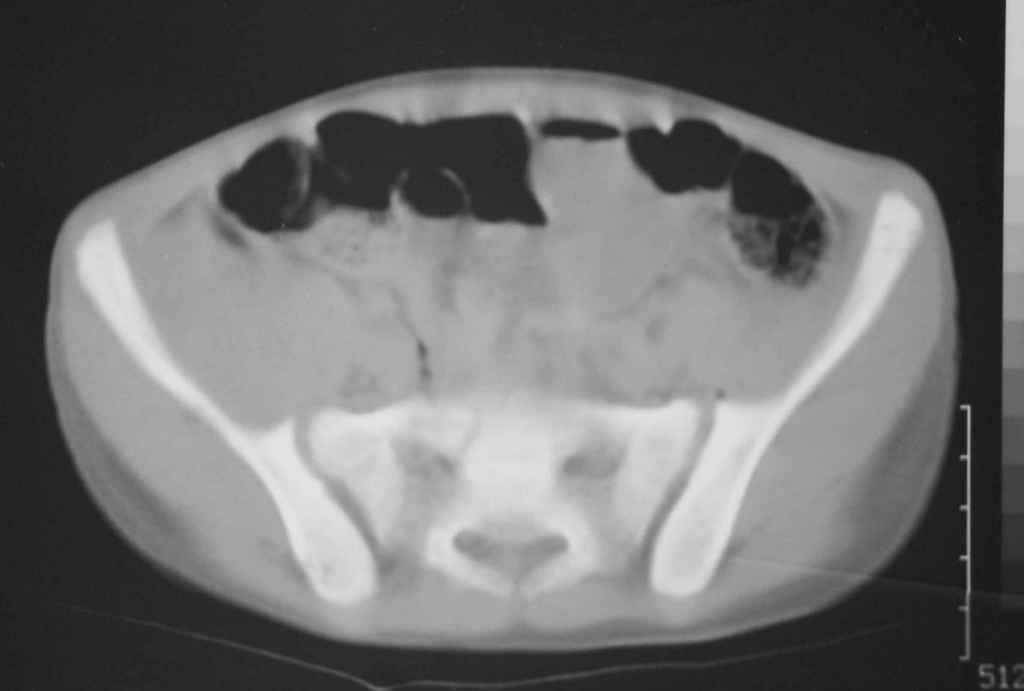

Перелом вертлужной впадины

Уважаемые коллеги, помогите определиться с тактикой лечения.Ребёнок 7 лет, травма 11.09.08, поступил с травматическим вывихом бедренной кости.

Вывих вправлен, конечность фиксирована на скелетном вытяжении. Что делать с переломом подвздошной кости? Лечить консерватино или оперировать?